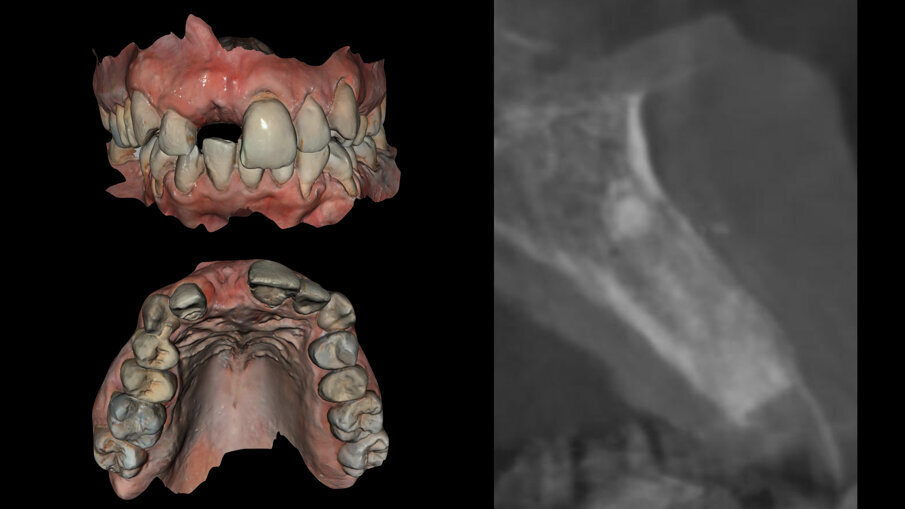

All’esame obiettivo generale la paziente presenta una malocclusione di 2a classe con recessioni multiple dei settori frontali e lateroposteriori, un sorriso gengivale e un fenotipo gengivale sottile e festonato con denti di forma triangolare, mentre a livello locale il dente 1.1 si presenta fortemente discromico con fistola apicale, recessione dei tessuti molli sia del 1.1 che del 2.1 di circa 3 mm con erosione cervicale (Fig. 2). Una prima indagine radiografica bidimensionale (rx endorale periapicale) evidenzia sul 1.1 una terapia canalare incongrua e radiotrasparenza apicale. Un esame tridimensionale CBCT evidenzia la discontinuità della corticale vestibolare identificata come classe 4 secondo Tarnow4, come esito dell’infezione apicale, ma rimane un ponte osseo crestale che sarà fondamentale per il percorso di ricostruzione dei tessuti duri e molli (Fig. 3).

L’esame CBCT è stato integrato con impronte digitali delle due arcate tramite scanner ottico Carestream 3600 (Carestream Dental Rochester New York Stati Uniti) e i file Dicom ed STL e la ceratura diagnostica digitale sono stati caricati in un software di programmazione chirurgica (3 Diemme srl Como) dove è stato progettato il posizionamento dell’impianto sull’1.1, impianto Imax 3.3 x 13 (Ires Group Mendrisio [CH]), da inserire tramite chirurgia guidata con dima chirurgica ad appoggio dentale5.